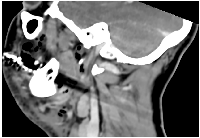

Early diagnosis is key to reducing mortality. Clinical suspicion should be confirmed with contrast-enhanced computed tomography (CT), which typically reveals fascial thickening, gas formation, and fluid collections along fascial planes [12, 13] (Figures 1 and 2). In some cases, magnetic resonance imaging (MRI) may offer higher soft tissue resolution, but its availability and speed are limiting factors in the acute setting [14]. Laboratory findings typically include elevated white blood cell counts, C-reactive protein (CRP), creatine kinase (CK), and lactate levels [15]. The Laboratory Risk Indicator for Necrotizing Fasciitis (LRINEC) score has been proposed as a diagnostic aid but has limited sensitivity in cervicofacial cases [16]. Several factors contribute to the reduced diagnostic utility of LRINEC in the head and neck region. First, gas-forming organisms, such as Clostridium spp., are less commonly involved in CNF than in infections of the trunk or limbs, which lowers the incidence of radiologically visible emphysema and correlating inflammatory patterns. Second, smaller anatomical compartments in the head and neck region may limit the extent of tissue destruction and systemic inflammatory response, particularly in the early stages—resulting in lower CRP, WBC, or creatinine values and thus underestimating LRINEC scores.